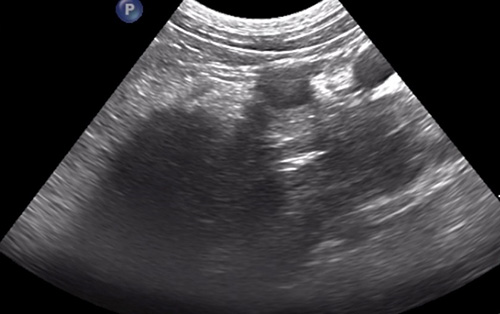

“When we performed a focal ultrasound of the area, we also found a foreign body (suspected to be a grass seed) at the very end of the abscess, close to the main vessels of the abdomen.

“The ultrasound meant we could see the foreign body which helped target the area and minimise surgical exploration in a very tricky spot, where some of the main abdominal vessels are situated.